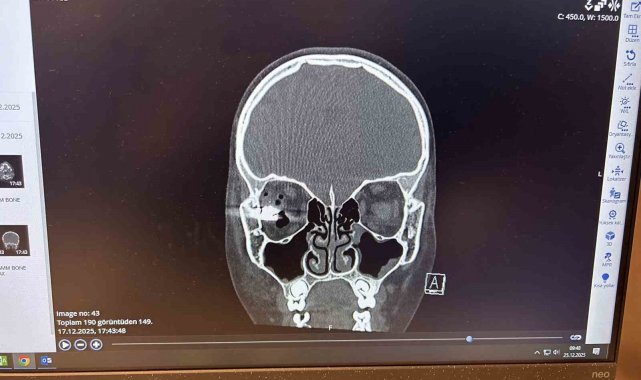

Özbekistan uyruklu 10 yaşındaki Ahrorbek Hojimurodov, Aralık 2025 tarihinde evde kuzeni ile birlikte silahla oynamaya başladı. Babası Bunyodjon Imomov'un uyarılarına rağmen çocukların oynadıkları silah bir anda patladı. Patlamanın etkisiyle silahtan çıkan mermi, Hojimurodov'un sağ gözüne çok yakın bir bölgeden beynine isabet etti. Babası tarafından ilk olarak Taşkent'teki bir hastaneye götürülen ve gözünü kaybetme riski bulunan Hojimurodov'a başarı oranı yüzde 40-60 olarak verildi. Bunun üzerine baba Imomov, oğlunu tedavi için Türkiye'ye getirerek Memorial Ataşehir Hastanesi'ndeki doktorlara teslim etti. Göz, plastik cerrahi ve beyin cerrahisi bölümlerinin koordineli çalışmalarıyla birlikte Hojimurodov'un ameliyatı başarıyla tamamlandı. Memorial Ataşehir Hastanesi Beyin ve Sinir Cerrahisi Bölümü'nden Prof. Dr. Zafer Orkun Toktaş, Hojimurodov'un tedavisinde kullanılan ve klasik yöntemlerden farklı olarak kapalı şekilde; adeta 'askeri dron sistemi'ne benzer yöntemlerle gerçekleştirilen 'Nöronavigasyon' teknolojili operasyonun detaylarını aktardı.

"Gerçekten bizim için unutulmazlardan biri oldu bu hastamız çünkü hem olayın oluş şekli hem de bize geliş şekli üzücüydü. Kuzeniyle oynarken bir silah yaralanması oluyor ve beyne son anda girmekten kurtulan ama maalesef göze doğru yönelen bir mermi vardı. Bu hasta bize yurtdışından ulaştı. Tabii ki biraz da teknoloji için ulaştığını düşünüyoruz çünkü gerçekten teknolojiye ihtiyacımız olan bir vakaydı. Bu vakada hem göz ekibi, hem plastik cerrahi ekibi hem de beyin cerrahisi ekibi ortak bir çalışma yaptı. Eski klasik yöntemlerde olduğu gibi biz bu hastada kafatasını açmadık. Ameliyatı gözden küçük bir kesi ile girerek gerçekleştirdik. Gözün dış duvarından navigasyon teknolojisiyle sadece 2 santimlik bir kesi yapılarak; yani halk arasında 'kapalı' olarak bilinen yöntemle çalıştık. Kemikte sadece merminin boyu kadar bir delik açarak bu mermi çıkartılmış oldu. Sonrasında hasta göz bölümüne devredildi, tamamen oranın takibi ve kontrolü altında şu anda ve sanıyorum ki o gözün görmesi de kurtarılacak, beklentilerimiz ve dileklerimiz bu yönde. Elbette ki çocuğumuzun hayatının kurtulması da bizim için ayrı bir sevinç kaynağı."